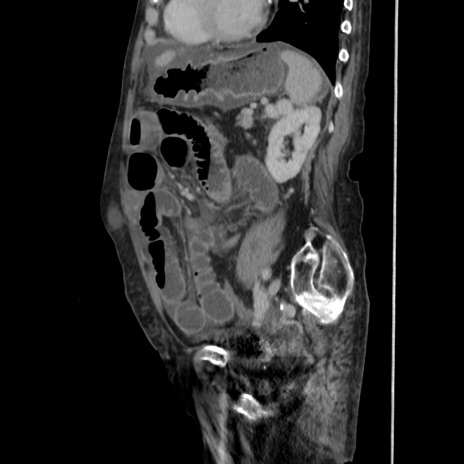

冠状断像

【症例】80歳代 女性

【主訴】腹部膨満感

【現病歴】他院にて肝硬変にてフォロー中。1週間前から便秘、腹部膨満感、臍部腫瘤あり受診となる。

【既往歴】肝硬変

【身体所見】腹部膨隆あり、皮膚変化なし、疼痛なし。

【データ】WBC 4600、CRP 0.25